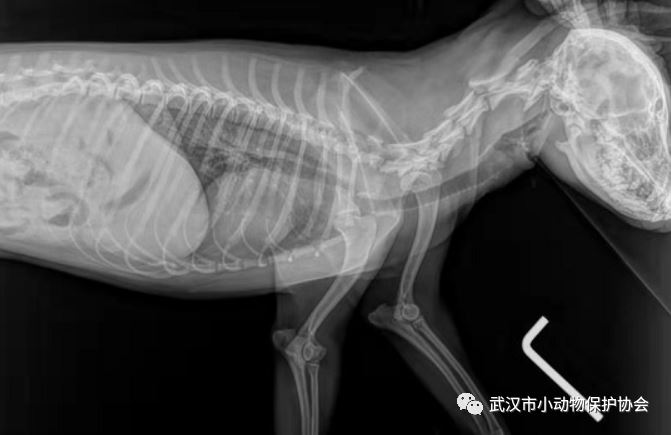

狗狗救助后带至动物医院拍片检查,发现确为车辆碾压导致的骨盆三处骨折(还有双侧隐睾),住院观察一段时间,择期手术。

动物信息:田园犬(比熊串)姓别:公年龄:约2 岁 取名:金城

金城的医疗费是4300元